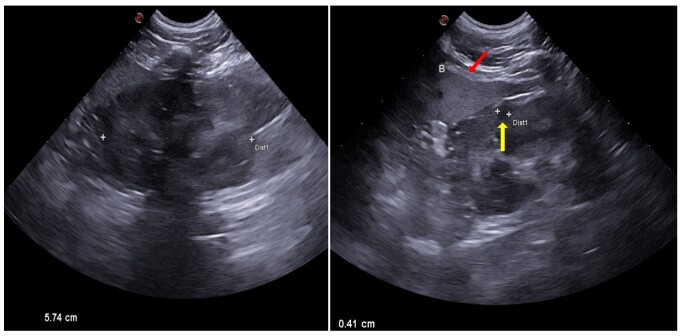

This study evaluated the effects of exposure to tobacco smoke on the kidneys of household dogs using B-mode ultrasonography and Shear-wave Elastography (SWE). Fifteen adult dogs were analyzed and divided into two groups: one exposed to passive smoking for at least two years (n=7) and another non-exposed group (n=8), both without a history of kidney disease. The animals underwent clinical evaluation and laboratory tests, followed by B-mode ultrasonography and renal elastography. Blood test were normal for all individuals. Ultrasonography demonstrated a significant increase in renal echogenicity (p=0.0070, for both right and left kidneys) and irregular contours (p=0.0256 for the right kidney, and p=0.0070 for the left kidney) in the exposed group. The variables echotexture, corticomedullary ratio, and presence of alterations did not vary between the groups (p>0.05). Tissues were harder in exposed dogs (p=0.0492). These findings indicate that exposure to passive smoking may compromise canine kidney health, with early alterations detectable through ultrasonography and elastography. This study highlights the importance of raising awareness about the risks of smoking in domestic environments and underscores the need for further research to deepen the understanding of passive smoking's impact on the renal morphology of domestic dogs.